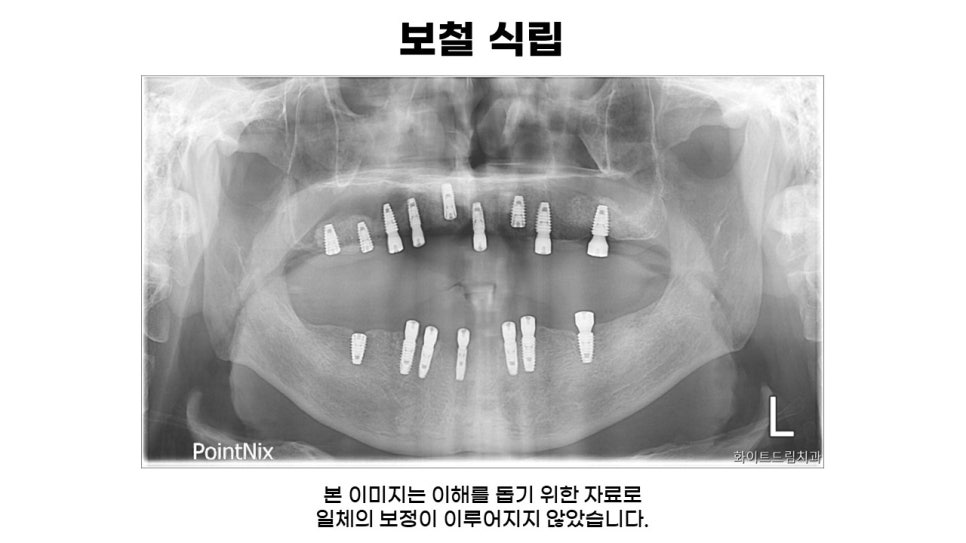

이어서 쉽게 확인해보실 수 있도록 준비한 식립 전 전체 파노라마입니다.

파노라마 상으로 확인해보니 전체적으로 잇몸뼈가 많이 무너져 내린 것을 확인할 수 있었습니다.

다음은 상악 좌, 우측 상악동 거상술 및 치조골 이식 후 보철식립 모습입니다.

상악동 거상술과 치조골 이식을 통해 보철식립 해드린 중간결과 모습과 전체 인상채득 후 보철이 완성된 모습인데요.

다수의 임플란트를 연결해서 보철물을 제작하는 등 파절과 재식립을 예방하기 위해 힘이 가해지는 각도와 위치를 고려하여 적절한 길이로 식립해 드린 모습입니다.